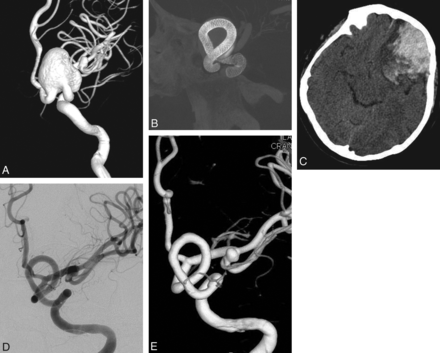

Preoperative 3D angiogram (A) shows a very wide-neck large ICA aneurysm. It could be reconstructed with several overlapping devices, creating a new vessel wall within the sac as seen on the perioperative DynaCT image (B). Postoperative CT obtained the same evening (C) reveals ipsilateral frontal intraparenchymal hemorrhage. 2D (D) and 3D (E) views of 6-month control angiography demonstrate the reconstruction of the parent artery and total occlusion of the aneurysm.

Two patients developed ipsilateral remote intraparenchymal hematomas. The first patient's hematoma developed within the first 8 hours after treatment (Fig 1). This hematoma was attributed to overmedication. The patient was placed on subcutaneous low-molecular-weight heparin despite her very high response to clopidogrel (the VerifyNow level was 97%) because the artery was reconstructed by using 16 devices overlapping in a telescopic fashion and we were worried about thromboembolic complications due to metal overload. The patient did not have any permanent neurologic sequelae from this event and was discharged home after 1 week. Control angiography showed total obliteration of the aneurysm with the parent artery reconstruction.